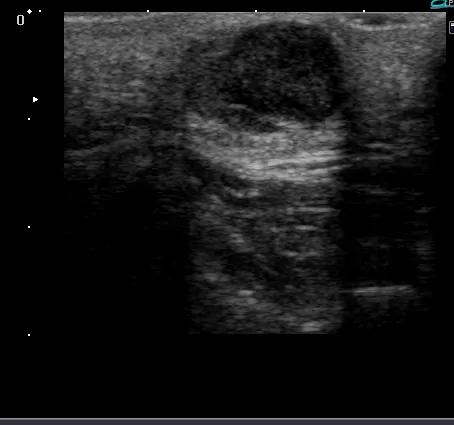

超音波検査では内部がエコーで後方エコーが増強しています。腫瘍近傍に血管も走行していません。(超音波検査)

超音波検査